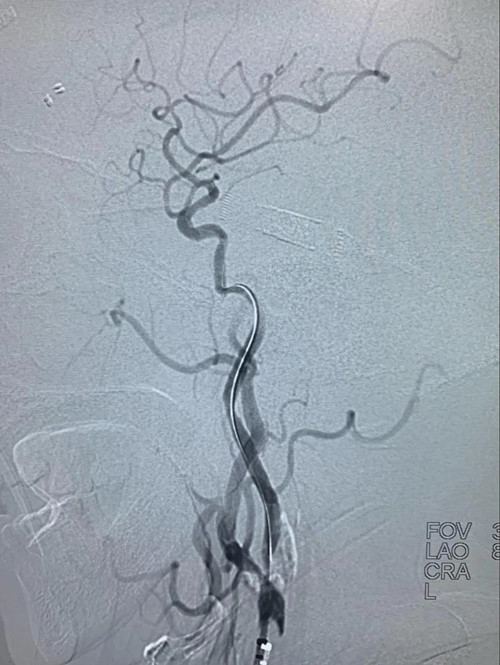

经取栓治疗后,原本闭塞不通的右颈内动脉-右大脑中动脉变得通畅无阻,但右颈内动脉闭塞处经球囊扩张成型后仍存在严重的“一线天”重度狭窄,随时可能在发生闭塞,与家属沟通后,决定为患者进行右颈内动脉支架植入彻底治疗病变。

右颈内动脉支架定位后释放支架,血管成型良好。

正侧位造影显示右颈内动脉-右大脑中动脉开通良好,血流恢复正常。